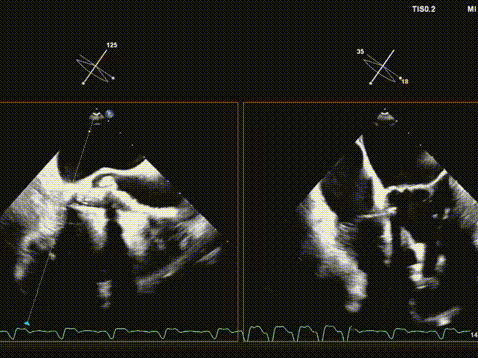

超声引导导丝跨瓣成功;

确认导丝在心尖部;

22mm球囊预扩;

输送系统顺利过弓及跨瓣;

快速起搏下初次释放瓣膜,瓣膜开口形态不好,位置偏高;

遂回收瓣膜,重新跨瓣并调整瓣膜释放位置后;

快速起搏下再次释放瓣膜至工作位,超声评估开口形态可,位置深度满意;

遂150快速起搏下完全释放瓣膜;

观察无瓣膜移动,回撤导丝后撤出系统;

术后超声评估,瓣膜位置深度满意,形态可,微量瓣周漏,最大血流速度1.53m/s,平均跨瓣压差4mmHg。